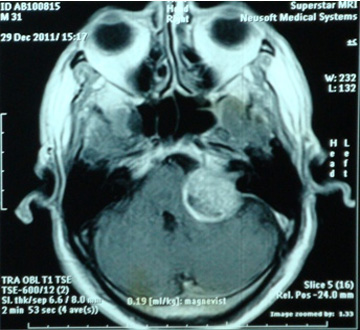

تومور در فضای بین مغز و گوش که زاویه پلی مخچه نامیده می شود، ایجاد می شود. آکوستیک نروما جزء تومورهای خوش خیم است اما خطر این تومور به دلیل رشد آن در فضای حساس و فشار آوردن آن به ساختارهای حیاتی مثل اعصاب جمجمه، مغز و ساقه مغز است. شایع ترین نشانه تومور شامل کاهش شنوائی در گوش مبتلا، وزوز گوش و عدم تعادل می باشد. برای بدست آوردن بهترین نتیجه، تشخیص صحیح به منظور انتخاب بهترین روش درمان در این اختلال ضروری است. برای تشخیص نورینوم آکوستیک انجام ام آر آی توصیه می شود. این روش تصویر برداری نه تنها به تشخیص کمک می کند بلکه وسعت و عوارض احتمال مانند هیدروسفالی را مشخص می کند.

نمونه های زیر MRI تعدادی از بیمارانی است که توسط دکتر اصغری جراحی شده اند: